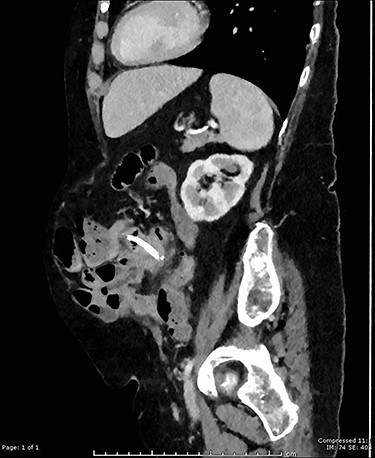

On examination, she had a large midline laparotomy scar, large reducible incisional hernia with localized peritonism in the left lower quadrant. She did not have generalized peritonitis. Biochemistry included a mild neutrophilia of 10.0 × 109/l (reference range 2.0–8.0 × 109/l), lactate of 2.6 mmol/l (reference range: 0.5–2.2 mmol/l) and C-reactive protein (CRP) of 125 mg/l (reference range < 2.0 mg/l). Cross-sectional imaging demonstrated a contained perforation around the migrated biliary stent within the incisional hernia (see Figs 1 and 2).

Sagittal CT image showing migrated biliary stent perforation through jejunum located within a large anterior abdominal wall hernia.